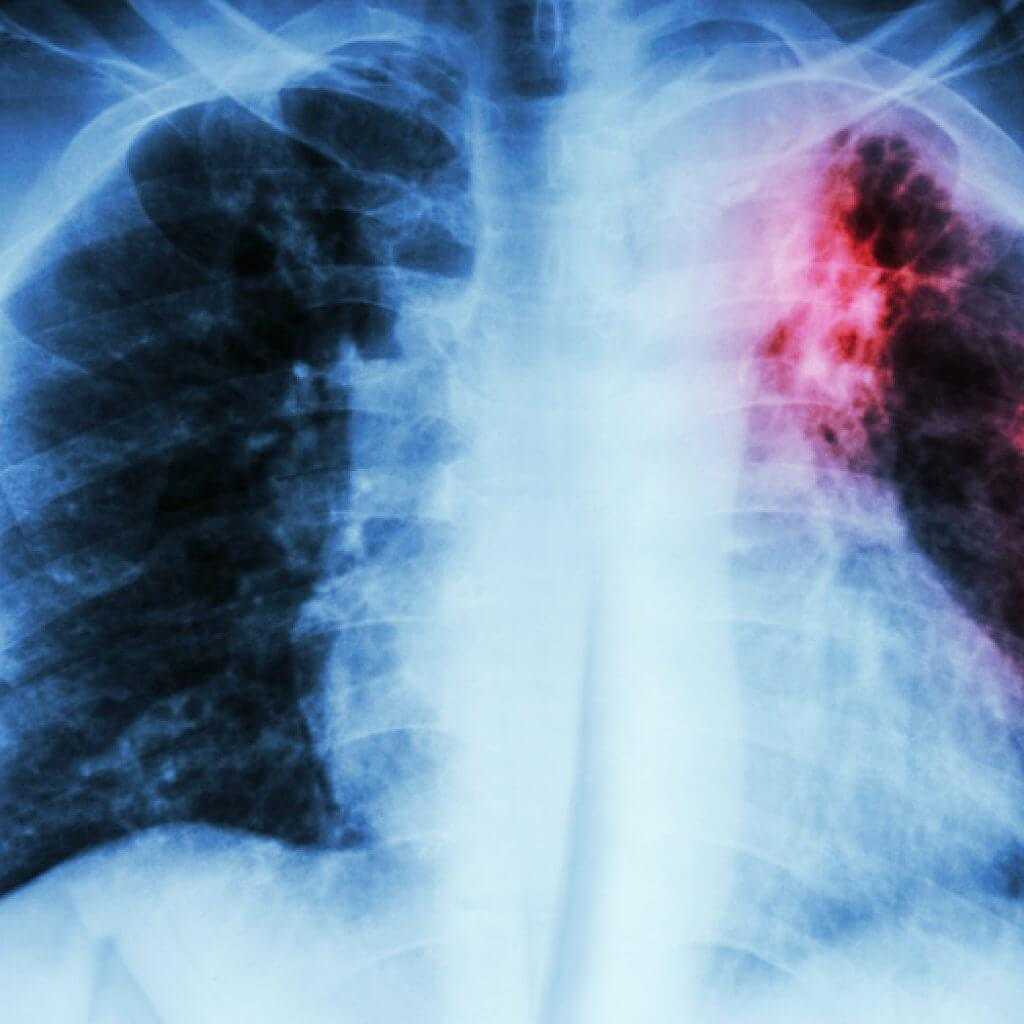

Рентгенологическое исследование легких проходит с помощью рентгеновского аппарата, который создает изображение внутренних органов на рентгеновской пленке или цифровом носителе. Пациент стоит или сидит перед аппаратом, а рентгенолог делает снимок, направляя лучи на грудную клетку. Процедура занимает всего несколько минут и не вызывает болезненных ощущений.

Рентгенологическое исследование легких позволяет выявить различные заболевания, такие как пневмония, туберкулез, рак легкого, эмфизема, фиброз легких и другие. Оно также может помочь в оценке состояния легких при хронических заболеваниях, например, при бронхиальной астме или хронической обструктивной болезни легких.

Иногда у пациентов возникает вопрос, зачем выполняется рентген легких в нескольких проекциях. Ответим, что обследование позволяет определить форму, размеры и характер патологической тени.

Согласно стандартам клинического обследования пациентов рентгеновскими лучами при подозрении на пневмонию врачи-рентгенологи делают снимки в прямой и боковой проекциях. По переднезаднему и боковому снимкам можно определить локализацию патологического образования, а также, сколько сегментов оно затрагивает.

В число патологий, что показывает рентген грудной клетки, входят разнообразные заболевания сердечно-сосудистой и дыхательной системы, а также грудного отдела позвоночника и непосредственно грудной клетки, то есть ребер и грудины. Что будет видно на рентгене, зависит от целей обследования.

Обзорная или общая рентгенография покажет все имеющиеся нарушения. К ним относятся:

- переломы и трещины ребер;

- искривленная грудина, аномалии строения и перелом грудины;

- аномалии позвоночного столба и ключиц;

- воспалительные и инфекционные повреждения тканей легких, в том числе пневмония и туберкулез;

- патологии сердца и сосудов.